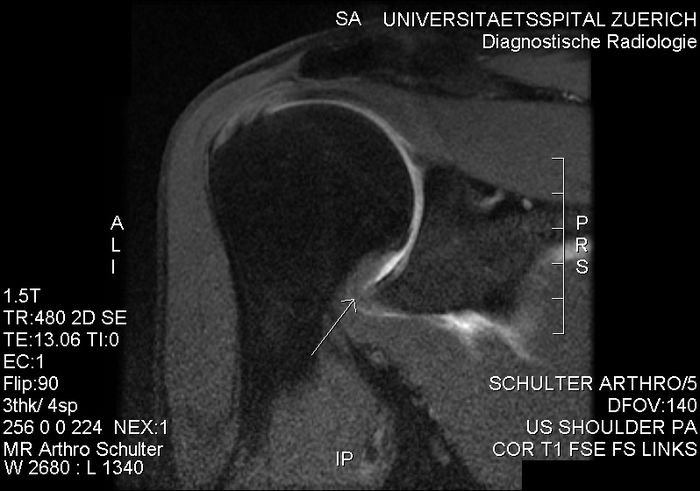

- Патологии ротаторной манжеты (РМ). Основной способ отличить патологии РМ от замороженного плеча - это изучение специфических ограничений в подвижности. Адгезивный капсулит проявляется ограничениями в капсулярном паттерне, в то время как в случае РМ ограничения обычно отсутствуют. Тендинопатия РМ может проявляться аналогично первой стадии замороженного плеча, так как ограничение наружной ротации минимально и тесты на силу могут быть нормальными. МРТ и ультразвук могут быть использованы для выявления мягкотканевых аномалий.